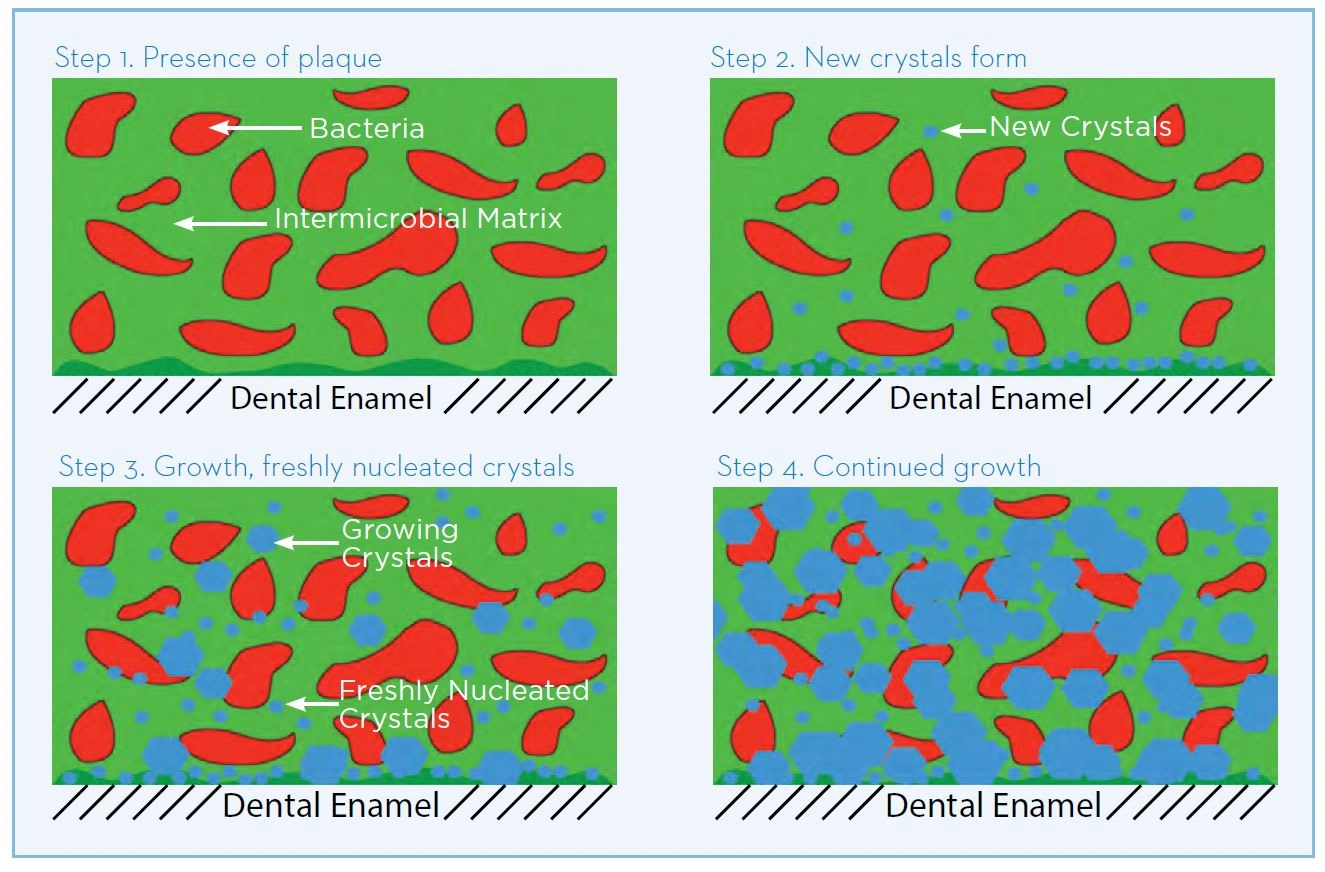

Figure 20. Hexametaphosphate molecule

Figure 20. Hexametaphosphate molecule

Pyrophosphate helps to reduce dental calculus through a mineral chelating effect that inhibits plaque mineralization. It has a natural binding affinity for calcium ions. The anticalculus effect is due to adsorption and binding of the pyrophosphate to the tooth surface and to forming crystals of calcium phosphate in plaque, helping to inhibit the growth and maturation of calculus (White & Gerlach 2000; Rykke & Rolla 1990; Rolla et al. 1988). Sodium hexametaphosphate (Figure 20) is a longer-chain form of pyrophosphate, with more binding sites. It has a greater affinity for hydroxyapatite surfaces, and binds strongly to the tooth surface and the surface of developing calculus in plaque. (Figure 21 White & Gerlach 2000; Baig et al. 2002, Busscher et al. 2002)